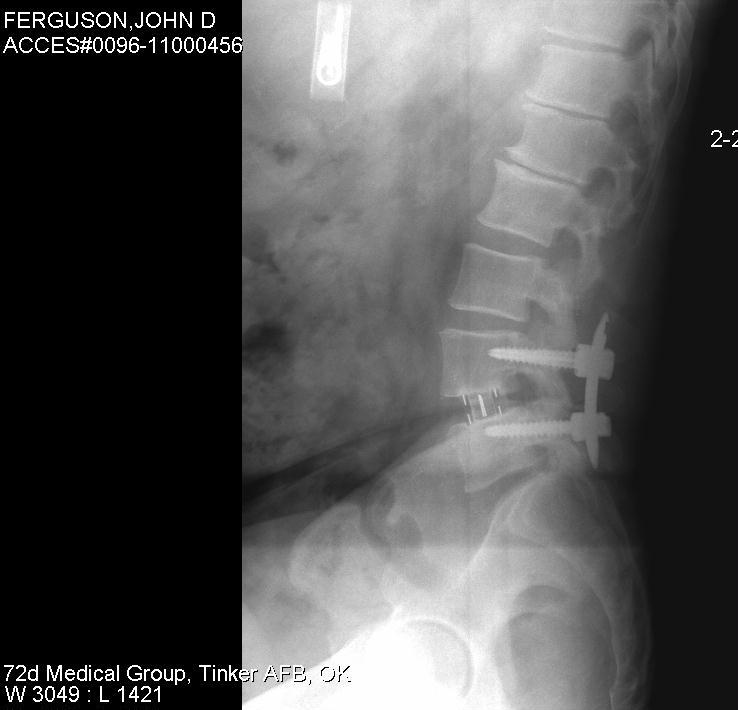

Like you, I know back pain well. I have a dead disc between my L4 and L5 vertebrae, as well as a bone spur that intrudes into my spinal nerve cluster, so I have suffered with shooting sciatica and back pain in various locations for many years - it really limits my mobility and what I can do. I can handle the pain fairly well, but what gets me is that I am limited when playing with my young 6 year old daughter. Of course insurance doesn't pay for disc replacement surgery and I refuse to get my spine fused, but C'est la vie... But as bad as back pain can be, just count your blessings that you don't have a kidney stone - now that's pain!